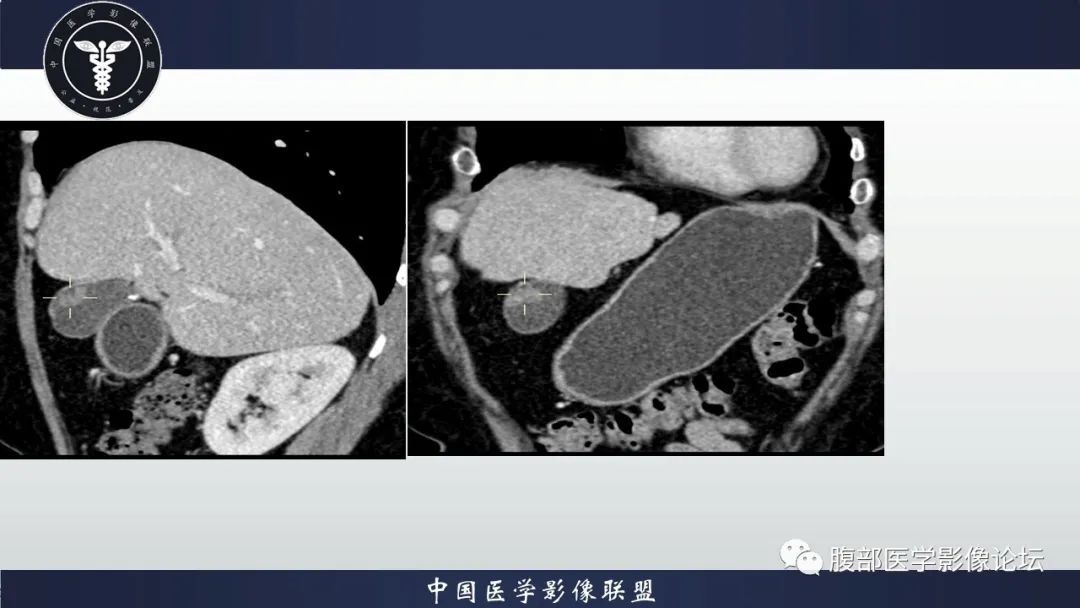

胆囊管状腺瘤1例CT及MR影像表现

【病例】胆囊管状腺瘤1例CT及MR影像表现-1